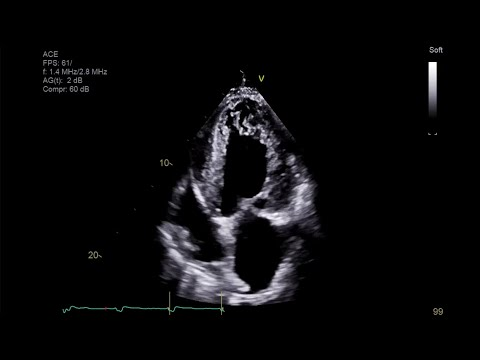

LV noncompaction CM

What is seen in this 2D image?